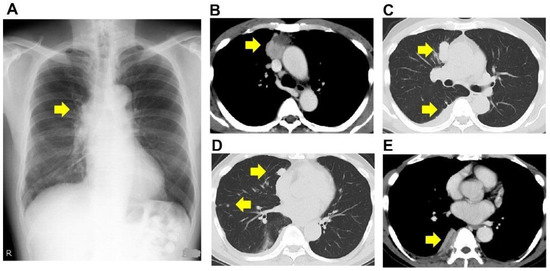

2. Case Presentation